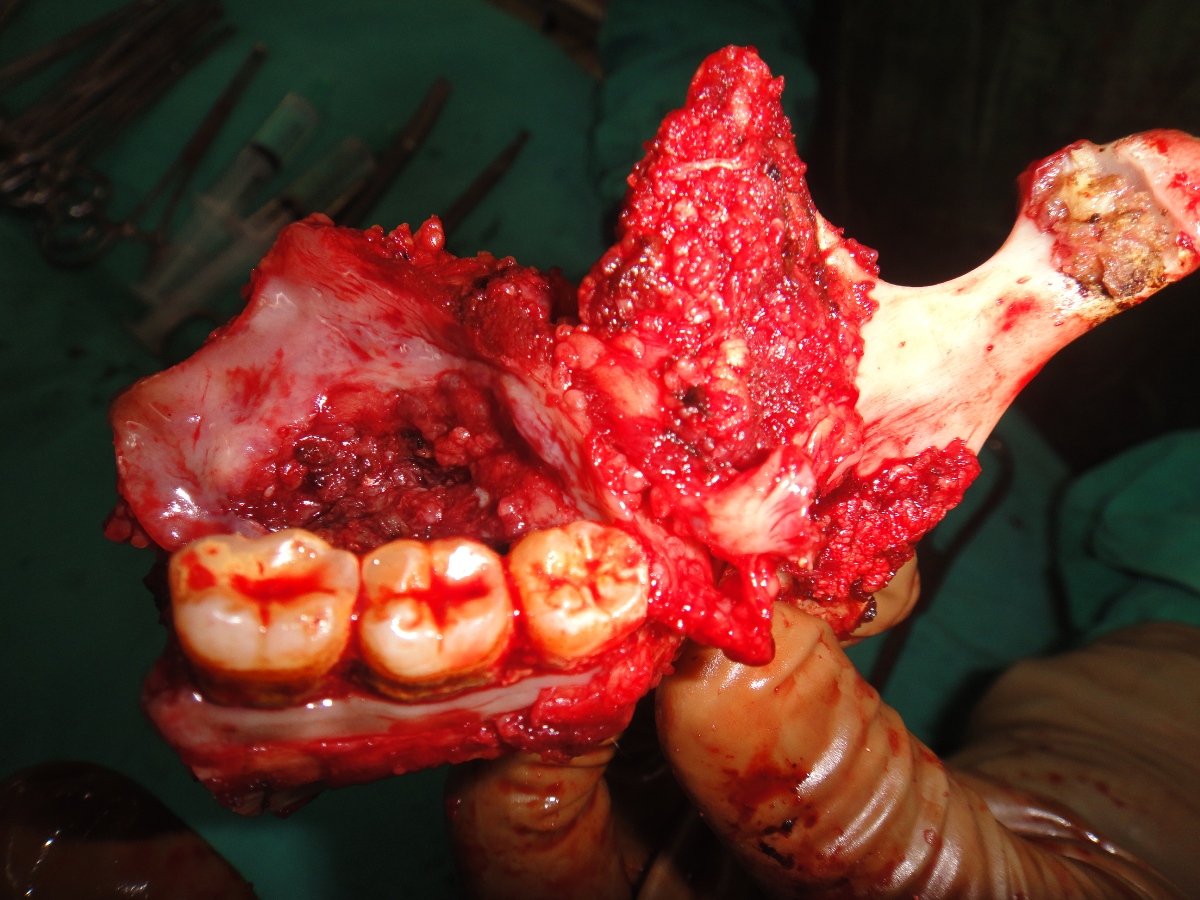

75 yrs old patient having right upper alveolus carcinoma.patient was operated for right buccal mucosa carcinoma in 2009.pet ct shows localised disease with minimal uptake in left neck node.Right subtotal maxillectomy done with Right PM flape.